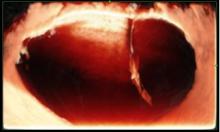

In seguito a questo grande impegno che sta continuando con il reclutamento di nuovi centri e di nuovi casi, ormai vi è in letteratura una forte evidenza che la valutazione soggettiva di una massa ovarica effettuata da un operatore dedicato attraverso l'ecografia sia un ottimo metodo per discriminare tra benignità e malignità ed in molti casi può essere suggerita pure una corretta diagnosi di natura della neoplasia sulla base della sola ecografia che, se associati alla clinica, all'esecuzione dei marcatori ovarici, aumentano ulteriormente la sensibilità nella diagnosi e nella stadiazione preoperatoria.

I progetti in essere prevedono l'esecuzione di ecografie ginecologiche di II livello di un operatore dedicato, atte a discriminare tra patologia benigna e maligna ovarica secondo la caratterizzazione della massa con i dati dello IOTA.

L’expertise dell’operatore, associato all’acquisizione da parte dell’Istituto di un’apparecchiatura di alto livello, dotata di software di ultima generazione anche con 3D e 4D, permettono di caratterizzare nei minimi dettagli l’eventuale presenza di patologia ovarica e di verificare l’eventuale disseminazione limitrofa agli organi circostanti. Questo da una parte dovrebbe permettere di evitare di misconoscere o sottovalutare alcune patologie ovariche potenzialmente evolutive in senso maligno e pertanto da indirizzare a trattamento chirurgico, e dall'altra di condurre un follow-up ecografico ad alcune patologie ovariche definite benigne secondo criteri standardizzati e ampiamente validati atti ad evitare una chirurgia non necessaria. Nel gruppo di lavoro IOTA infatti si è visto in questi anni che quasi l'80 percento delle masse ovariche operate risultavano benigne. E’noto che ogni procedura chirurgica è associata a possibili complicanze a breve come a lungo termine.